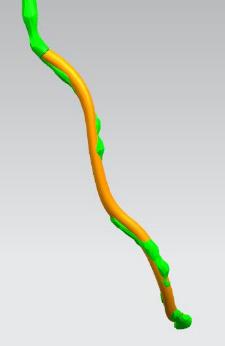

其次在对应的病灶位置进行一定的细节修改,或改变其形状或改变颜色以便于突出显示病灶位置。

模型细节修改